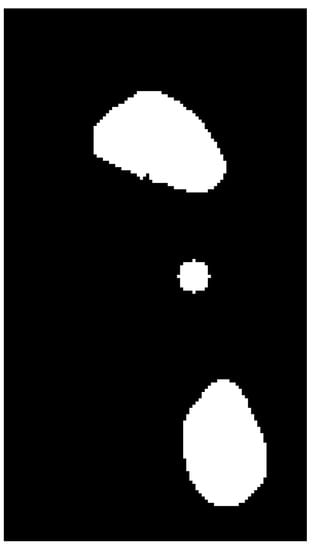

The first technique is the segmentation (separation) of the desired regions, which are the areas of greatest pressure in the front and back of the foot. The representation of the selected regions and the center of the contour of the entire foot is shown in Figure 7.

Regions with the highest intensity of pressure are highlighted, which correspond to the red spectrum (warmer colors, such as red, are fields of high pressure on the ground). The segmented region (footprint with toeprints removed) can be seen in Figure 8.

Figure 7. The regions of greatest pressure and the center of the contour of the entire foot.